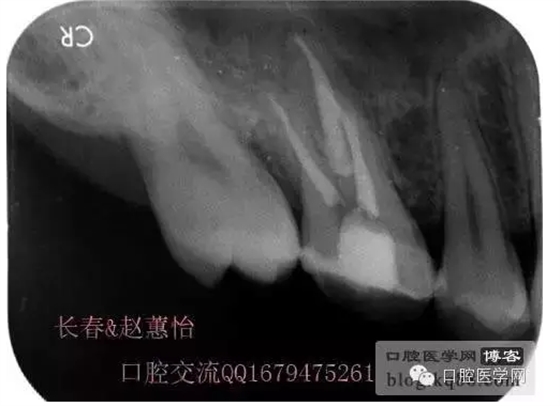

看多了文字眼花繚亂了吧,今天一個(gè)根管內(nèi)有臺(tái)階的患牙被充填上了,刻意投照了N多的X光片終于有一個(gè)給力的了,仔細(xì)觀察,可以看得見喔,也算是辛苦努力給個(gè)安慰獎(jiǎng),很多都是從片子上看不出有什么不同的。

這個(gè)是術(shù)前照片,一切如常

患牙是死髓牙,患者是一位大學(xué)生,探查根管時(shí)一切都很順利,就有點(diǎn)忽視了,當(dāng)然這個(gè)臺(tái)階是人為造成的,造成的原因呢就是使用機(jī)擴(kuò)時(shí)跳號(hào)了,所以大家一定要逐號(hào)使用啊,預(yù)備出一個(gè)臺(tái)階,后續(xù)要搭上很長(zhǎng)時(shí)間才能搞定,好不容易越過(guò)臺(tái)階下去的銼,一提拉出來(lái)就下不去了,著實(shí)讓人郁悶,一切都要從頭再來(lái),這個(gè)時(shí)候再下銼的時(shí)候就必須預(yù)彎了。而且要多角度試探,很是考驗(yàn)?zāi)托牡臅r(shí)候。吃一塹長(zhǎng)一智嘛!

術(shù)后,明顯可見近中頰側(cè)根管臺(tái)階位置

越過(guò)臺(tái)階后小心預(yù)備直至大錐度銼可以順利進(jìn)術(shù)前片的小彎沒當(dāng)回事,哎